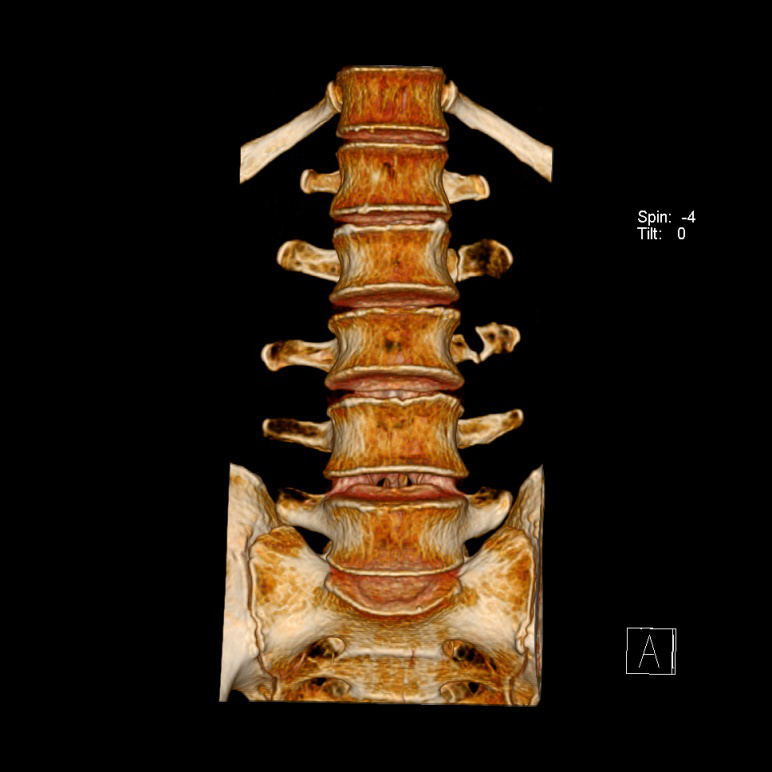

图5 腰2、3椎体陈旧性骨折

根据检验所见赖XXL2、L3左侧横突骨折,断端骨皮质局部连续,断端圆钝、硬化,结合案情分析认为,赖XX腰2、3椎体左侧横突骨折系本次外伤前即存在的陈旧性骨折,且骨折时间较长,与本次外伤无直接因果关系,不宜据此进行损伤程度鉴定。横突新鲜性和陈旧性骨折在CT片上的区别主要根据断端形态,一般横突新鲜性骨折,断端锐利,骨折线清晰,而横突陈旧性骨折一般断端有愈合,若分离较大至骨不连,断端会呈现圆钝、硬化改变。